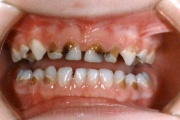

Vali sind huvitav pilt ja me näitame sellega seotud haigust ja sümptomeid